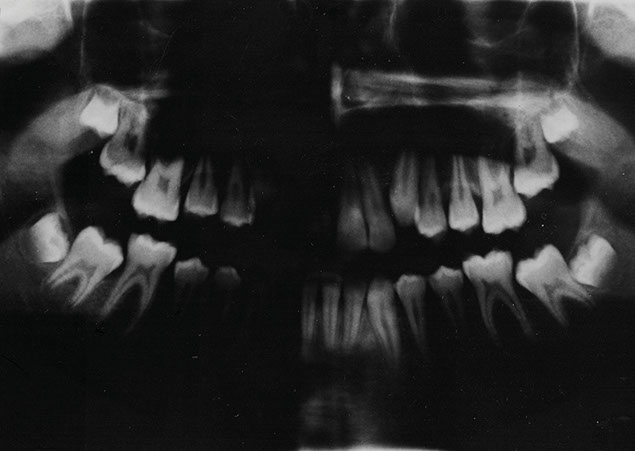

The 148-page art book 'KOBES' is inspired by an old notebook of my grandfather, Prof. Dr. Kobes, who spent his lifetime researching and determining of new butterfly species as a hobby besides his job as a professor of dentistry. The book's narrative is led by the naive grandson who never had a real idea of what he was doing all the time and is now trying to understand the meanings of the technical language that is used by the expert.